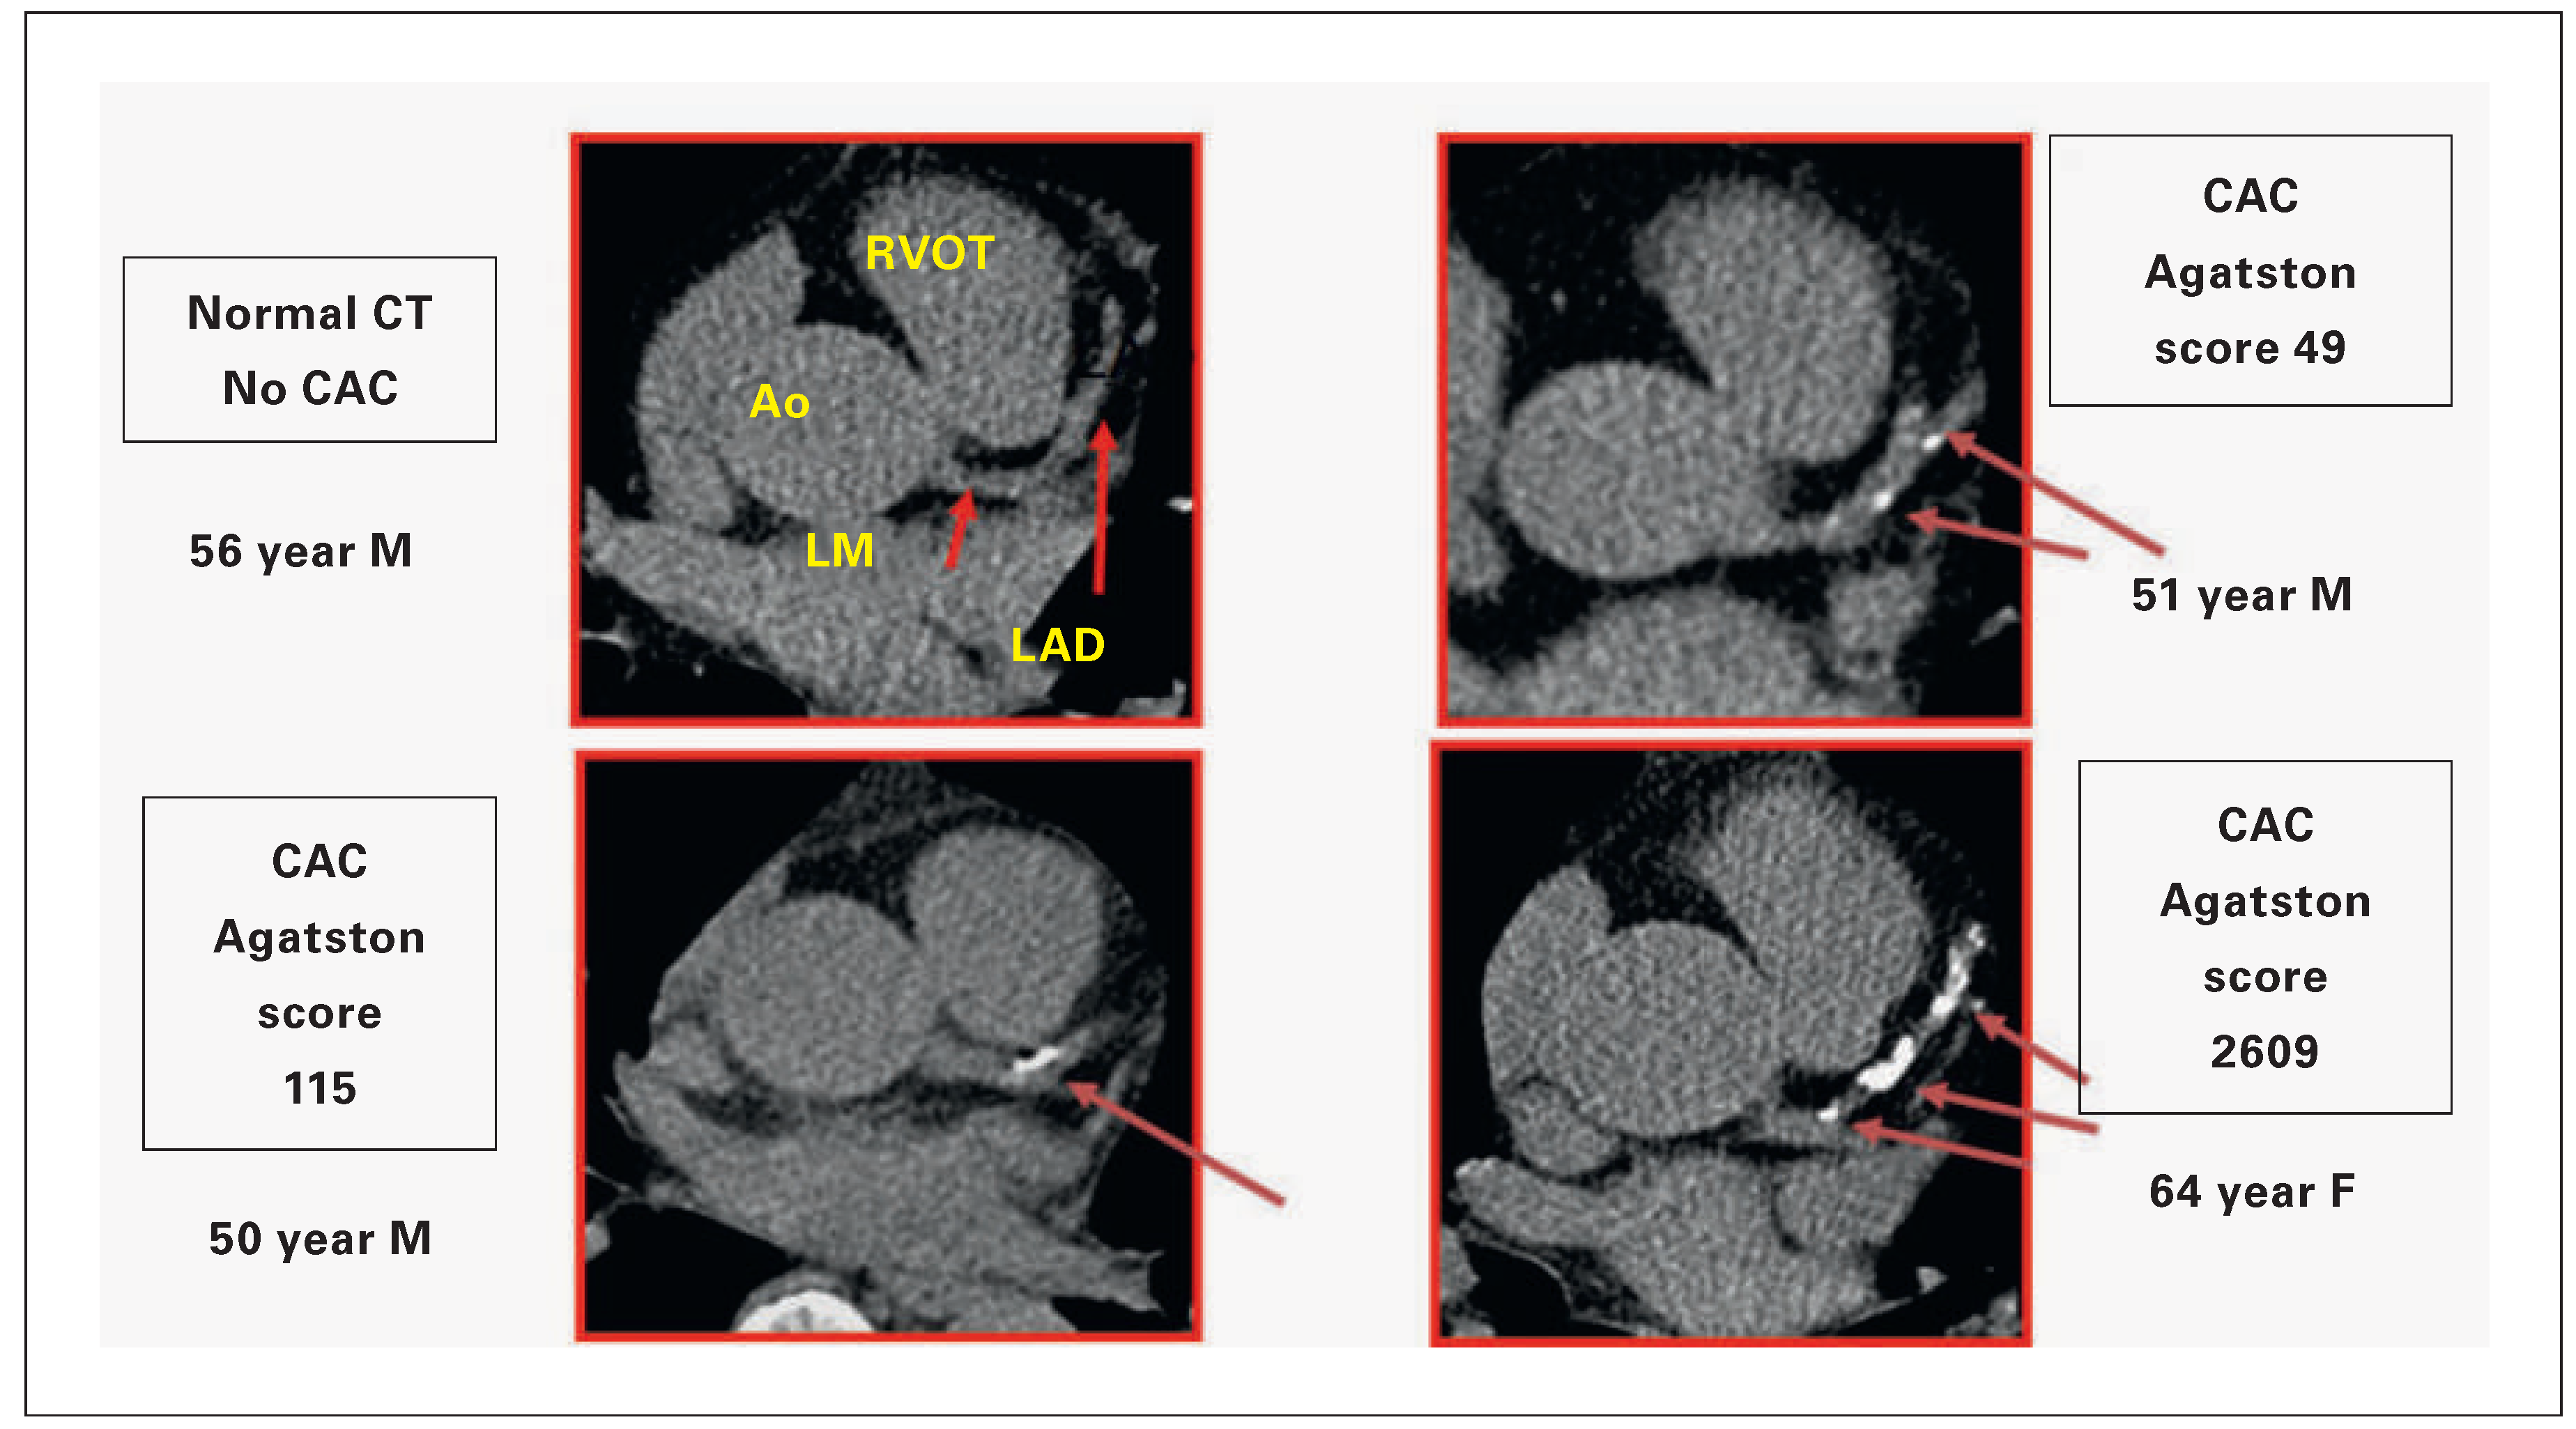

Figure 2. Signs of subclinical coronary artery sclerosis detected in men and women (m/w) at the age of 50–65 years with increasing calcium load: 0, 0–49, 115 and 1609 Agatston Score. Visualised is a typical slice at the level of the origin of the left main coronary artery from the aorta, showing the proximal left descending coronary artery distal to the bifurcation. AO = Aorta; LAD = left anterior descending coronary artery; LM = left main coronary artery; RVOT = right ventricular outflow tract.

With modern technology the quantification of CAC is possible and reproducible. In comparison to other methods, CT is the noninvasive technique to best detect signs of subclinical atherosclerosis (Figure 2). If the density is ≥130 Hounsfield units, a calcified plaque is present. A plaque is defined if ≥4 adjusted pixels are found. This density can be related to a density factor between 1 and 4 (≥130–199, 200–299, 300–399, ≥400) and multiplied with the area of the plaque which leads to the Agatston Score [25]. The usual slice thickness is set at 3 mm and all slices in which plaques can be identified are summed up. Thus, the Agatston Score gives the total amount of calcification, but can also be related to vessels or even vessel segments.